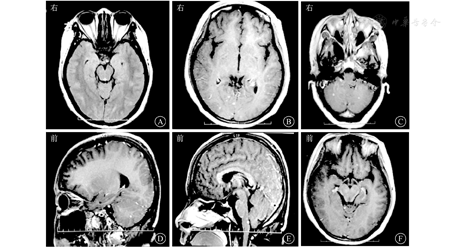

患者女,27岁,因"间断发热、头痛11个月,肢体麻木、纳差1 d"于2015年5月29日收治武汉市医疗救治中心。2014年5月患者因原发性不孕行体外受精-胚胎移植术,其后间断低热,8月下旬经超声检查提示死胎,即在外院行清宫术。9月下旬发热症状再次加重,在外院经抗感染治疗后一度好转。11月初患者再次出现发热,体温多在39 ℃左右,伴头痛、呕吐,经青霉素640万U,2次/d抗感染治疗后未见好转。反复在外院就诊,2014年11月9日行腰椎穿刺查脑脊液结果示白细胞计数55×106/L,乳酸脱氢酶35 U/L,总蛋白2 278 mg/L(表1);结核感染T淋巴细胞斑点试验阳性。11月10日行头颅MRI提示脑干、双侧小脑半球、双侧额叶及右侧颞叶异常强化灶(图1),诊断为结核性脑膜脑炎。彩色多普勒超声示子宫壁多发性钙化灶,子宫后壁囊性包块,考虑合并生殖系统结核。否认既往特殊病史。婚育史:患者20岁结婚,婚后7年内未避孕情况下未能正常受孕。予异烟肼0.4 g/d、利福平0.45 g/d、吡嗪酰胺1.25 g/d联合抗结核治疗后病情渐有好转,除吡嗪酰胺治疗5个月后停药外,其余药物持续应用于整个抗结核疗程中。2015年5月28日患者突发急性脑梗死,表现为吐词不清、左上肢乏力,遂入院治疗。6月2日复查头颅MRI见新发脑梗死病灶,但脑膜强化减轻(图2),6月5日查脑脊液相关指标好转(表1),加强抗结核治疗(异烟肼0.4 g/d、利福平0.6 g/d、吡嗪酰胺1.5 g/d、对氨基水杨酸钠8.0 g/d、阿米卡星0.6 g/d、左氧氟沙星0.6 g/d),辅以脱水、抗感染等治疗后好转出院。2015年7月19日患者突发运动性失语进行性加重,右侧肢体麻木,活动受限,伴有胸闷、气促,感疲乏无力,再次就诊,头颅MRI提示颅脑梗死病灶较前明显,但脑膜强化较前减轻(图3),2015年7月22日再次查脑脊液结果示总蛋白441.4 mg/L,白细胞计数、氯化物、葡萄糖等指标无异常(表1)。体格检查:神志清楚,反应稍迟钝;颈软,颈动脉搏动正常,双侧颈动脉未闻及血管杂音;双侧瞳孔等大等圆,对光反射灵敏,右眼外展不到边;伸舌右偏;右侧上肢肌力4+级,右下肢肌力4级,右侧Babinski征阳性,Kernig征阴性,右侧腱反射亢进,提示右侧肢体偏瘫。进一步行头颅磁共振血管成像(magnetic resonance angiography, MRA)示双侧大脑前、中动脉不显影、侧支循环增粗紊乱,Willis环特征性改变符合烟雾病(图4)。继续完善实验室检查,结核蛋白芯片检测38 000蛋白、脂阿拉伯甘露糖及结核分枝杆菌抗体-IgG均阳性,结核感染T淋巴细胞斑点试验阳性,抗核抗体谱2、抗中性粒细胞胞浆抗体、梅毒螺旋体抗体阴性;颈动脉彩色多普勒超声无异常;肿瘤标志物阴性;一次脑脊液抗酸染色阳性,因此排除其他感染、占位等因素,再次确认结核感染诊断,综合以上结果,诊断为结核性脑膜脑炎合并烟雾病。维持原方案抗结核治疗,并给予甘露醇稳定颅内压、地塞米松、吲哚布芬抗感染、营养神经、改善脑循环及防治血管性痴呆等治疗,患者脑梗死相关症状逐渐好转,肢体功能恢复,生活可以自理,而后出院继续服药治疗,治疗过程中定期复查腰椎穿刺脑脊液检查及头颅MRI检查等,抗结核治疗2年后复查头颅MRI提示脑膜强化等基本吸收(图5),抗结核治疗2年满疗程停药。